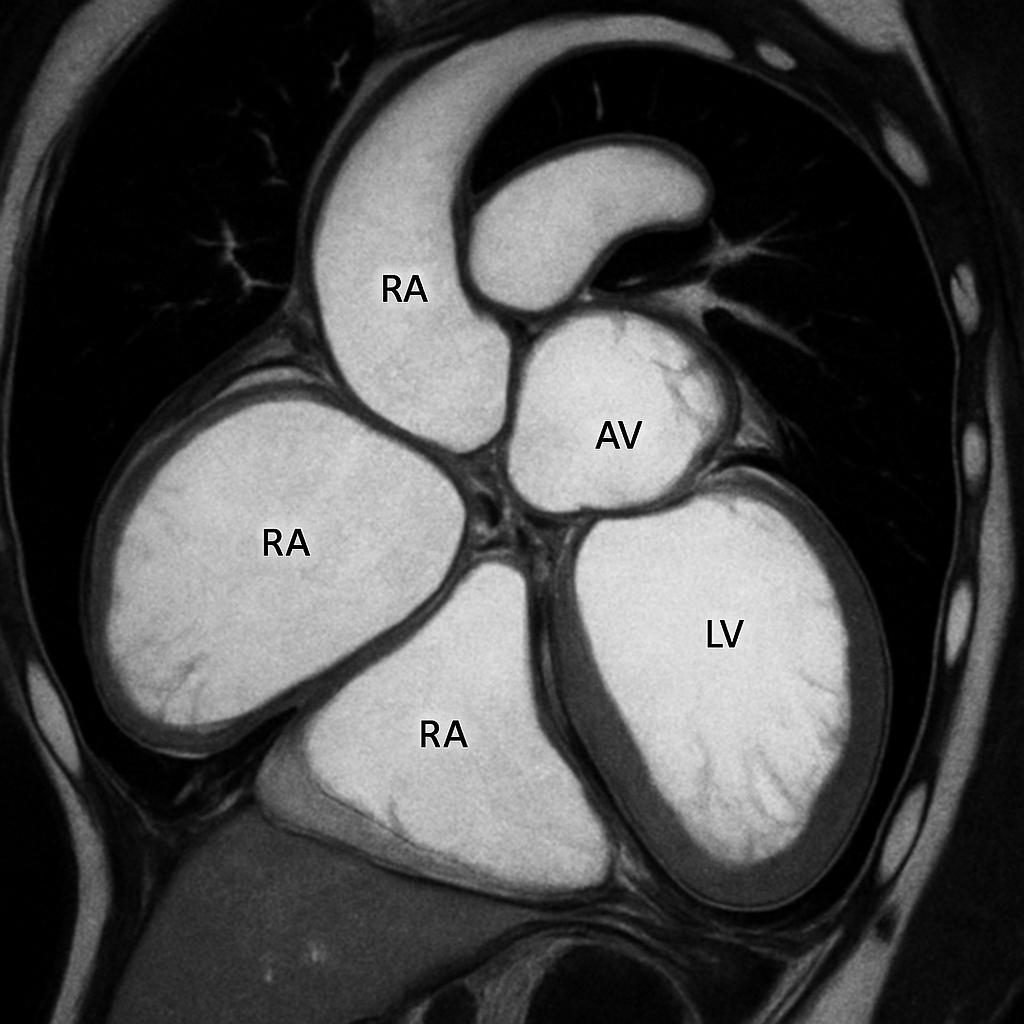

MRI — Four-Chamber View

Cardiac MRI four-chamber (4CH) long-axis view showing all four chambers, both AV valves (mitral and tricuspid), interventricular and interatrial septa. SSFP bright-blood.

MRI AI Generated 2026-03-16

Ssfp Four Chamber

bSSFP cine, four-chamber view. Show all chambers, AV valves, septa. Bright blood.